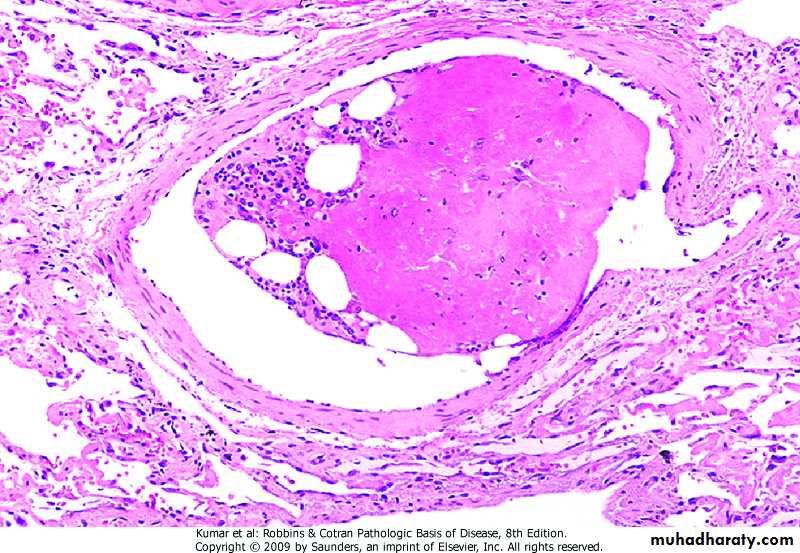

INFARCTION

Ischemic necrosis due to occlusion of either artery or vein

Causes:- Thrombosis or embolism (99%)

- Local vasospasm

- Expansion of atheroma

- Extrinsic compression of a vessel (tumor, twisting, edema, hernia)

- Traumatic rupture of vessel

Morphology - Most infarcts are wedge-shaped, with occluded vessel at the apex and periphery of the organ forming the baseInfarcts are classified on the basis of:

At the outset, all infarcts are poorly defined and slightly hemorrhagic, in few days, they become more firm and brownMost infarcts are replaced by scar tissue

Red infarcts occur in: - Venous occlusion (testis, ovary) - Loose tissue - Tissues with dual circulation - Previously congested tissues - Re-established blood flowWhite infarcts occur in: - Arterial occlusion - Solid organs with end-arteries

A. Hemorrhagic infarct lung B. white infract spleen